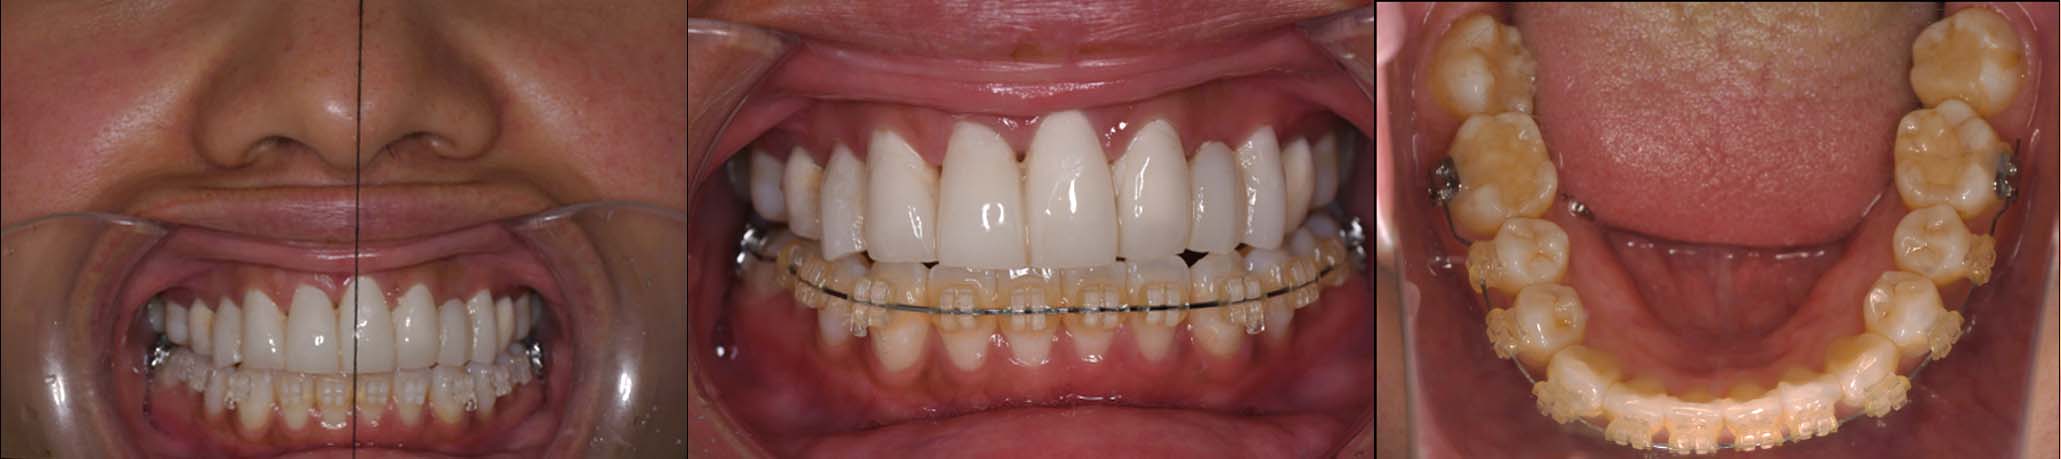

| 治療内容 | ①スプリントを装着 ②副子を装着 ③2024年4月 口腔内反映開始 ④副子を入れた状態の所まで咬合を挙上 (バイトアップ) ⑤2024年5月 上顎前歯部8本へ仮歯(TEK) を装着 |

バイトアップ後